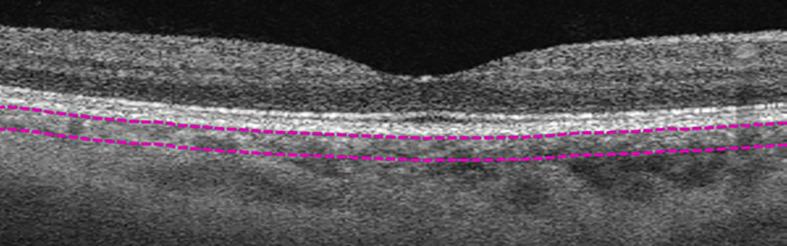

METHODS

This is a clinic-based observational study of 148 eyes with axial length (AL) ≥25mm, enrolled from the high myopia clinic of the Singapore National Eye Centre. MMD was graded from fundus photographs. Swept source OCT (SS-OCT) and OCTA were performed and assessed for choroidal layer thickness (CT) and choroidal vasculature (choroidal vessel density (CVD), choroidal branch area (CBA) and mean choroidal vessel width (MCVW)) in the different choroidal layers (overall choroidal layer (CL), medium-vessel choroidal layer (MVCL), large-vessel choroidal layer (LVCL)).

使用光学相干断层扫描血管造影(OCTA)评估和比较患有和未患有近视性黄斑变性(MMD)的高度近视成年人的脉络膜形态学血管参数。

方法

这是一项基于临床的观察性研究,对148只眼轴长度(AL)≥25mm的眼睛进行研究,这些眼睛来自新加坡国家眼科中心的高度近视诊所。根据眼底照片对MMD进行分级。进行扫频源光学相干断层扫描(SS - OCT)和OCTA,并评估不同脉络膜层(整体脉络膜层(CL)、中血管脉络膜层(MVCL)、大血管脉络膜层(LVCL))的脉络膜层厚度(CT)和脉络膜血管系统(脉络膜血管密度(CVD)、脉络膜分支面积(CBA)和平均脉络膜血管宽度(MCVW))。